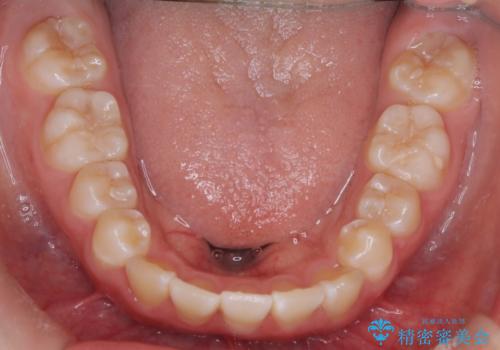

【インビザライン】前歯を下げたい

- 前歯が出ていることを主訴に来院されました。

インビザラインにて奥歯の遠心移動を行いながら最大限前歯が下がるように治療を行いました。

今回は遠心移動とIPRによってここまで前歯を下げることができました。